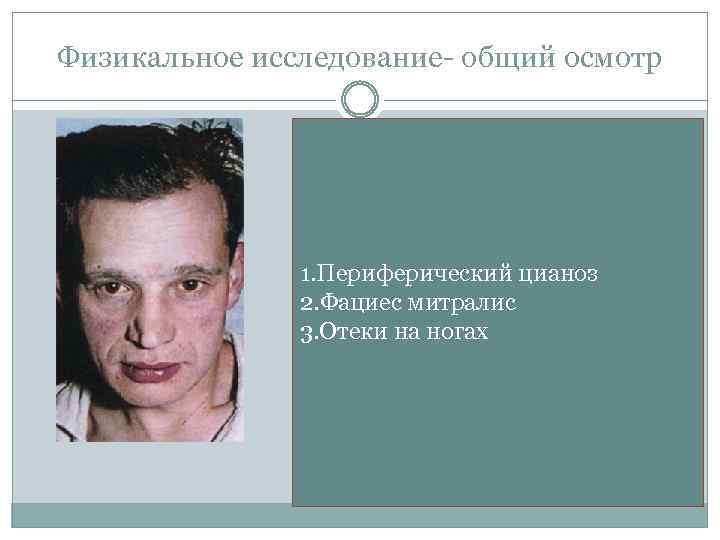

Физикальное исследование- общий осмотр 1. Периферический цианоз 2. Фациес митралис 3. Отеки на ногах

ОСМОТР: Фациес митралис: «митральный румянец» (при развитии легочной гипертензии) на фоне бледной кожи, цианоз кончиков пальцев рук, мочек ушей.